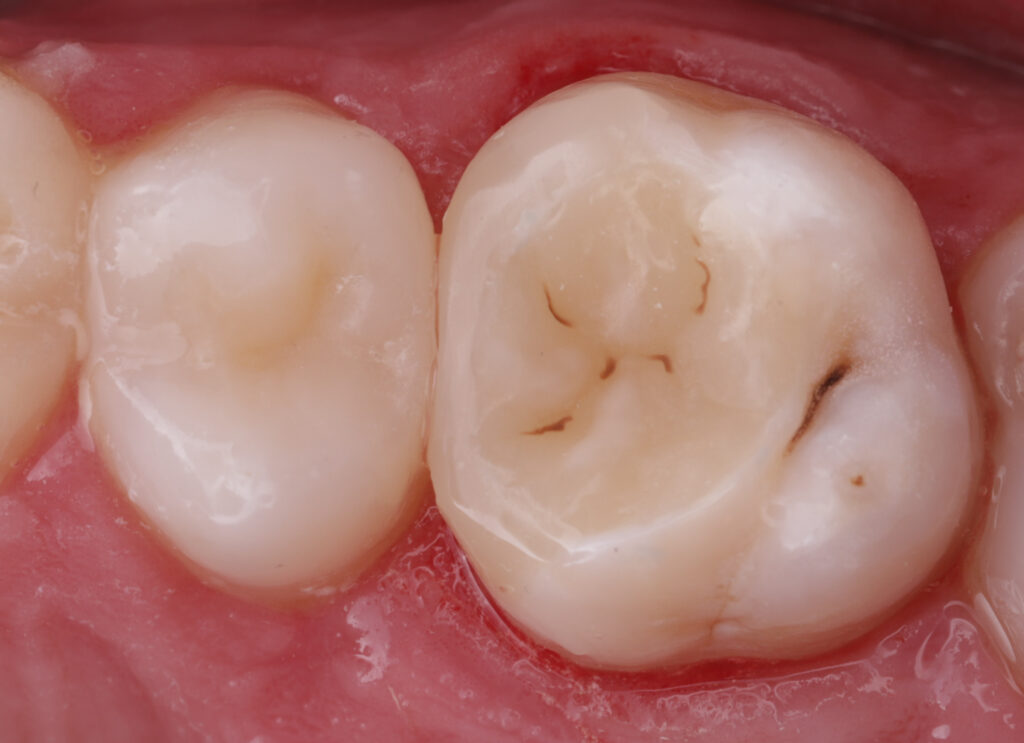

During the first visit, all carious tissues were removed, and the missing wall was restored using Asteria A3B material. The root canals were de-obturated, and a missed MB2 canal was identified. The canals were temporarily obturated with calcium hydroxide.